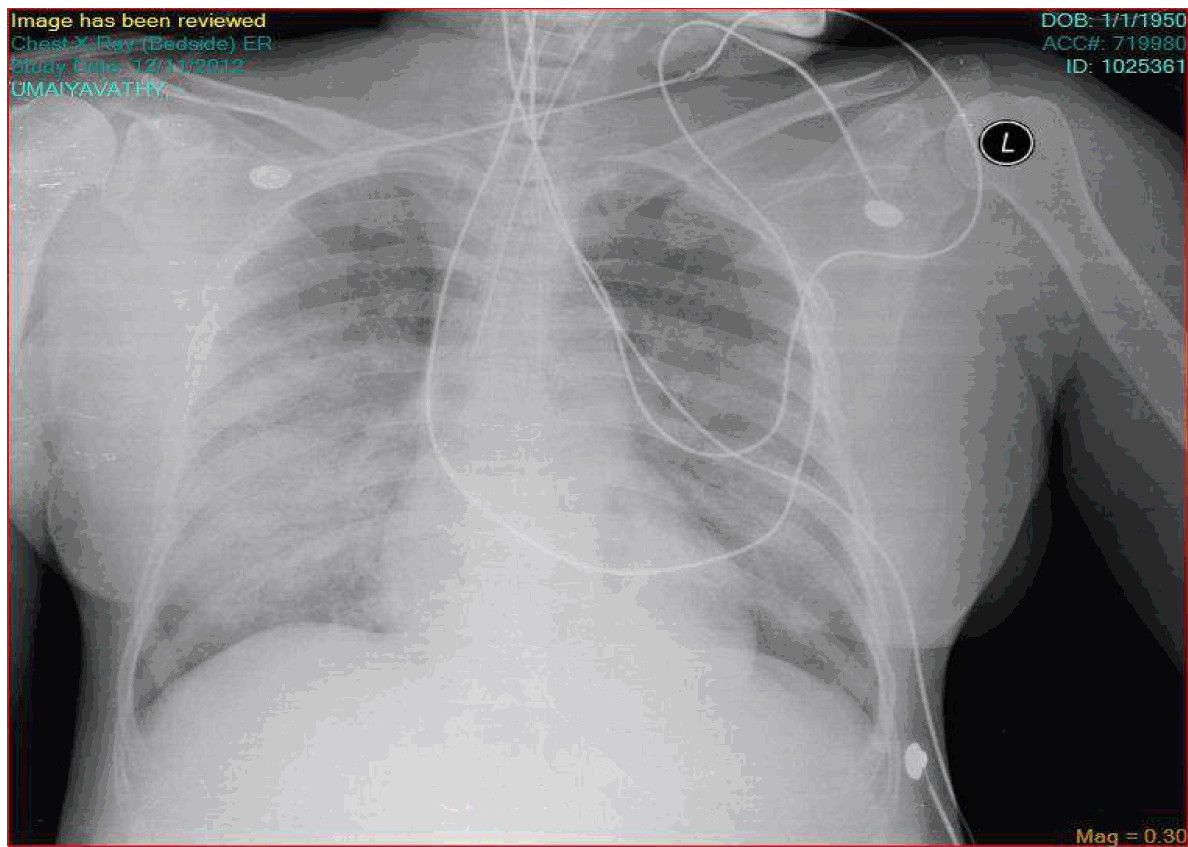

A 62-year-old female, farmer by occupation presented to the emergency department with history of high grade fever and chills for three days. She was managed with antipyretics in outside hospital with no benefit. She developed breathlessness at rest for 1 day. Hence she was referred to our institution for further management. On examination, she was febrile (101°F) and tachypneic with a respiratory rate of 40 per minute. Her pulse rate was 106 per minute and her blood pressure was 110/80 mmHg. She had an eschar in her right loin. Her respiratory examination revealed bilateral extensive crepitations. Her jugular venous pressure was normal and she was clinically euvolemic. We proceeded with the following investigations as given in Table 1. Arterial blood gas revealed type 2 respiratory failure (pH 7.04, pCO2 7.5 mmHg, PO2 57 mmHg). In view of progressive breathlessness despite supportive measures she was intubated and connected to a ventilator. Chest X-ray showed features of consolidation (Figure 1) which was subsequently confirmed by CT scan of thorax (Figure 2). The patient developed altered sensorium subsequently. CT scan of brain was normal. Cerebrospinal fluid (CSF) analysis showed sugar of 72 mg/dl, protein 67 mg/dl, 140 WBC/hpf, neutrophils 65% and lymphocytes 35%. CSF culture, gram staining, HSV serology done were negative. Etiologic workup for fever, ARDS, and altered sensorium were done (Table 2). Patient was initially managed with broad spectrum antibiotics - imipenem plus cilastatin and linezolid. After serology report of scrub typhus being positive she was started on doxycycline 100 mg BD and rifampicin 600 mg OD. On day-3 of admission patient developed blackish discoloration of the terminal digits of upper and lower limbs which was progressive in nature and ultimately developed into dry gangrene (Figure 3) and (Figure 4) over 4–5 days. However, all her peripheral pulses were felt normally. Vasculitis workup like ANA, dsDNA, antiphospholipid antibody, C-ANCA, P-ANCA, Anti centromere antibody were negative. Vascular surgery opinion was sought and the patient was started on LMWX and aspirin. Biopsy of the lesion was not attempted as the patient's relatives did not give consent. After eight days of doxycycline therapy patient showed gradual improvement in clinical condition and was weaned off from ventilator subsequently. Patient developed severe pain in her upper and lower limb digits around the gangrenous areas. She received several analgesics including tramadol, amitriptyline, paracetamol, NSAIDS with partial relief of pain. She was started on cilostazol, aspirin, pentoxifylline by vascular surgeon after cessation of LMWH. She eventually developed auto amputation of her right lower limb second and third toes followed by second toe of left lower limb and little finger of her right hand over the next 2–3 months. | ||||||